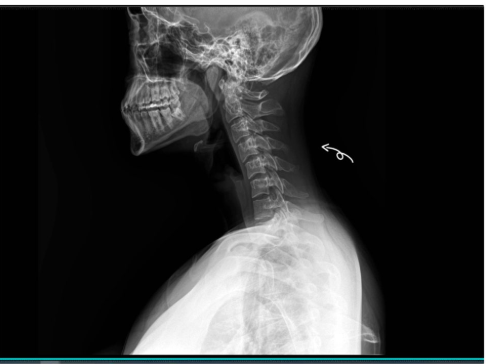

평소 어깨가 자꾸 앞으로 말리고, 목이 앞으로 나가는 느낌을 받으신 적 있으신가요?

왜 거북목과 굽은등은 쉽게 반복될까요?

굽은 등과 거북목은 단순히 ‘잘못된 자세’ 때문만은 아닙니다.

인간은 본래 에너지 절약을 선호하는 동물이라, 편한 자세를 반복하면 그 형태가 굳어버립니다.